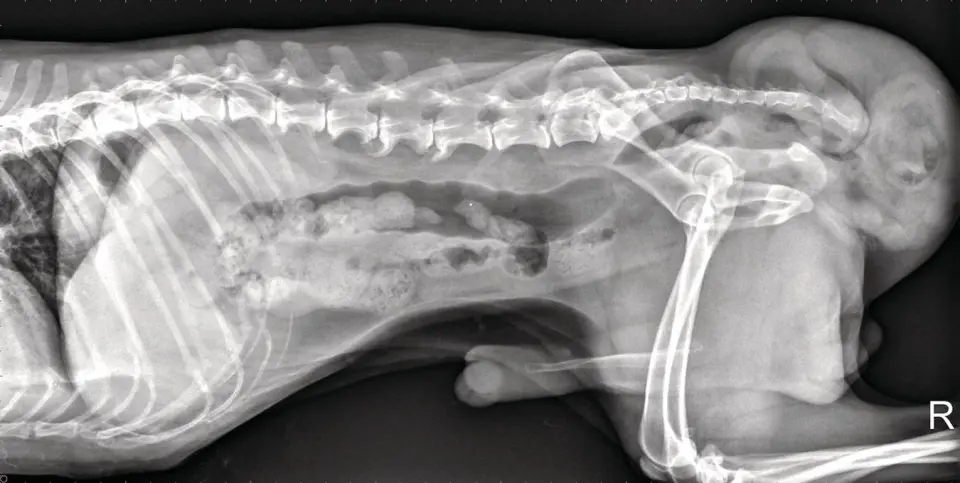

狗單側會陰疝氣X光圖

就診對象:

7 歲未結紮公狗,體重約 16 公斤。

就診原因:

飼主發現狗狗肛門左邊有一顆鼓鼓的包,已經三個月,越來越大。

最近排便困難、要用力很久才排出,還因此變得食慾不好。

臨床檢查:

檢查時發現肛門左邊的腫塊柔軟、可輕推移動,像麵團一樣。

用手從直腸內觸診,可以感覺到乾硬的糞便團塊。

狗狗精神狀況良好、生命徵象穩定,

綜合評估後診斷為單側會陰疝氣——也就是肛門旁的肌肉鬆弛,導致腹腔內的脂肪或腸子鼓出來。